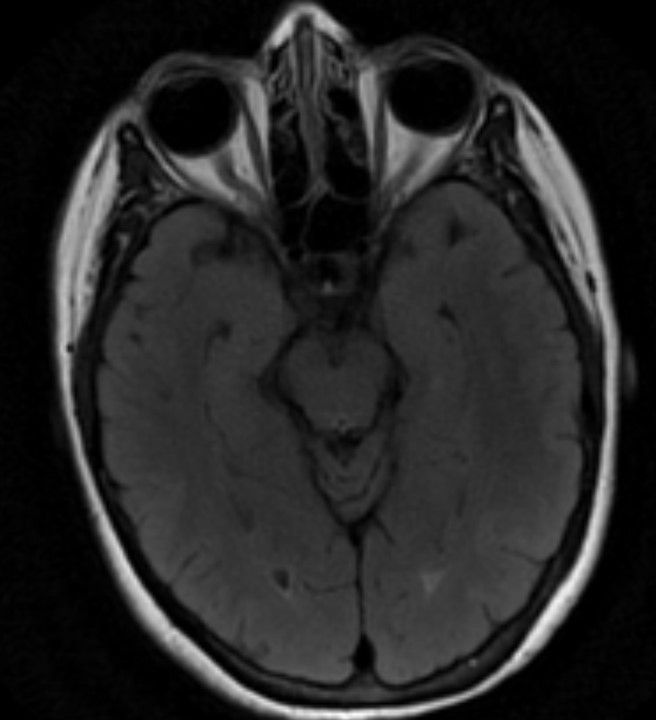

Image IQ Quiz: 57-Year-Old Female with Altered Mental Status

A 57-year-old female presents with an altered mental status. What do the images reveal?